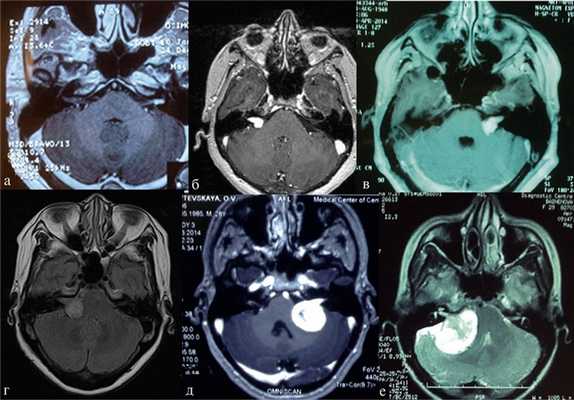

Три стадии роста вестибулярной шванномы:

а - Опухоль с интрамеатальным ростом.

б - Опухоль с интра- и экстрамеатальным ростом.

в - Опухоль с преимущественно экстрамеатальным ростом.